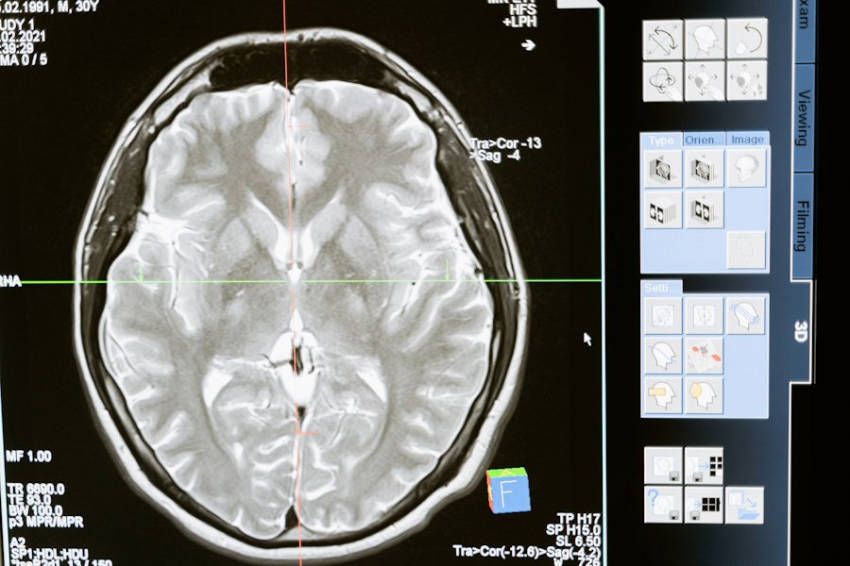

Фото из открытых источников

Новое исследование в University Hospital of Nimes (Франция) показало, что высокие дозы витамина D3 (холекальциферола) значительно снижают активность заболевания у пациентов с клинически изолированным синдромом (CIS) — ранней стадией рассеянного склероза (РС). Об этом сообщают результаты рандомизированного контролируемого исследования, представленные на 40-м Конгрессе Европейского комитета по лечению и исследованию рассеянного склероза (ECTRIMS) 2024 года.